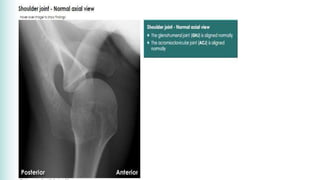

• An Axillary view is essential; it shows posterior subluxation

or dislocation and sometimes a deep indentation on the

anterior aspect of the humeral head.